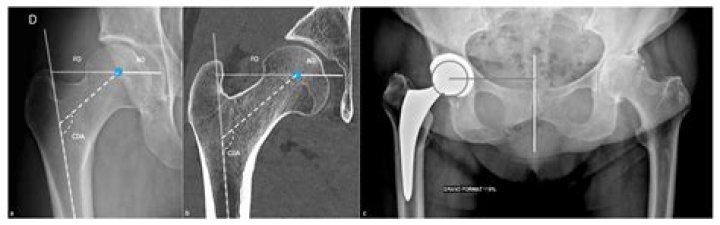

The hip joint (see the image below) is a ball-and-socket synovial joint: the ball is the femoral head, and the socket is the acetabulum. The hip joint is the articulation of the pelvis with the femur, which connects the axial skeleton with the lower extremity.

The natural size of the femoral head usually ranges from 40 to 54 mm, with smaller sizes usually found in females. In the initial development of hip arthroplasty, artificial femoral heads were designed to replicate these anatomical dimensions.